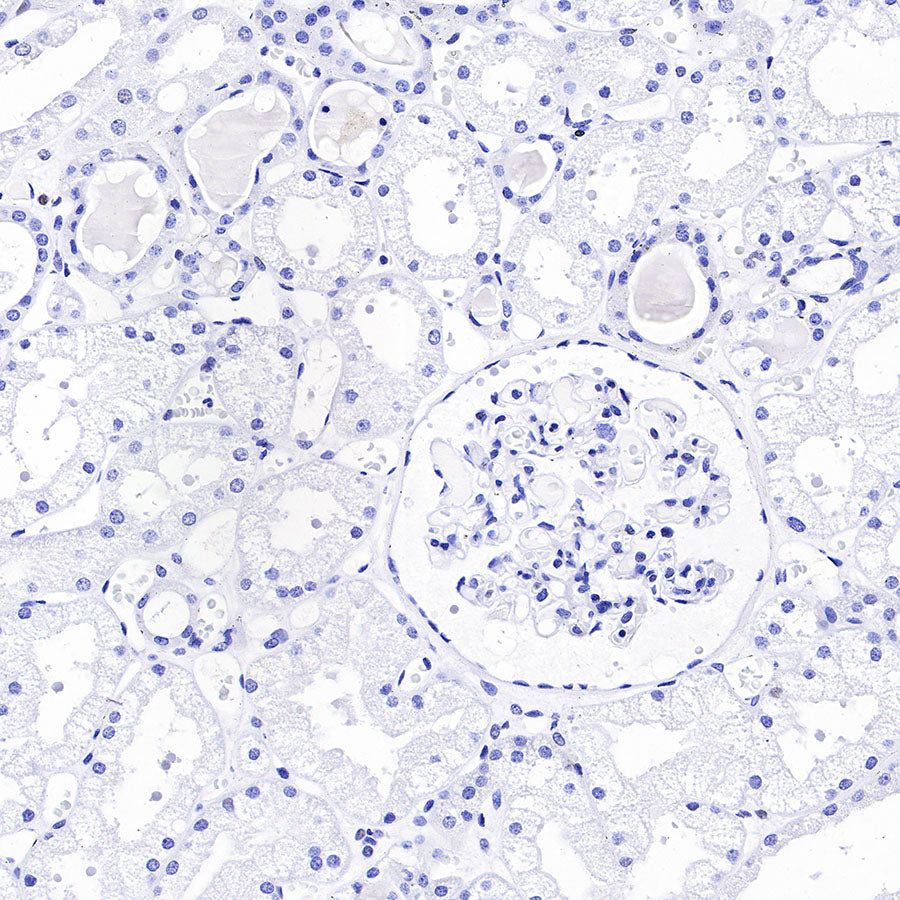

Immunohistochemistry

| IHC-P | 1:1000 | null |